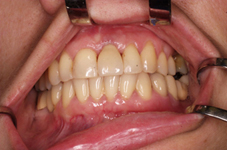

Během let může postupnou ztrátou zubů zůstat v ústech omezený počet zubů, které umožňují držení zubních náhrad.

V důsledku přetížení zbylých zubů např. houpavými pohyb snímacích náhrad dochází k uvolnění těchto zubů a držení můstků a protéz je tak velmi těžké. V těchto případech můžeme pomocí implantátů zvýšit počet pilířů a tím zabránit přetěžování a ztrátě zbylých zubů